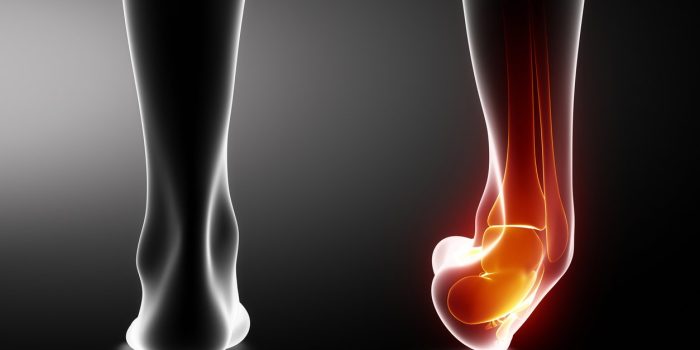

شکستگی مچ پا به معنای آسیب دیدگی استخوان مچ پا است. این نوع شکستگی ممکن است ناشی از تصادفاتی مانند تصادف با اتومبیل یا سقوط و افتادن از پلهها باشد. شدت شکستگی مچ پا متفاوت است و میتواند از شکستگی کوچکی در مویه استخوان تا شکستگی کامل و بیرون زدن استخوان از پوست متغیر باشد. درمان شکستگی مچ پا بستگی به محل و شدت دقیق آسیب دیدگی دارد. در صورتی که شکستگی مچ پا شدید باشد، ممکن است نیاز به جراحی و استفاده از ایمپلنت، میله یا پیچ در ناحیه مچ پا باشد. این اقدامات باعث حفظ استخوان شکسته در موقعیت مناسب میشوند تا بهبودی بهتری را برای بیمار به ارمغان بیاورند.

مفصل مچ پا از سه استخوان تشکیل شده است – نازک نی، درشت نی و استخوان مچ پا (استخوانی است که پا را به انگشتان متصل میکند).

رباطها وظیفه اتصال استخوانهای بدن به یکدیگر را بر عهده دارند تا ثبات مفاصل را فراهم کنند. زمانی که مچ پا پیچ خورده یا شکستگی مچ پا رخ دهد، رباطها معمولاً آسیب میبینند. این آسیب میتواند باعث ناپایداری مچ پا شود. یکی از رباطهای مهم در داخل مچ پا، رباط دلتایی است که وظیفه ایجاد ثبات مچ پا را دارد. در صورتی که رباط دلتایی به دلیل شکستگی مچ پا پاره شود، مچ پا به طور کلی ناپایدار میشود.

در مفاصل مانند مچ پا و گوشتخواره و هر نوع مفصل دیگری در بدن، دو یا چند استخوان به صورت هم جهت با یکدیگر حرکت میکنند. بین استخوانها، غضروف نامیده میشود که به عنوان یک بالشتک یا پوشش عمل میکند. تنش یا آسیب در این ناحیه میتواند منجر به آرتروز یا التهاب مفصل شود.